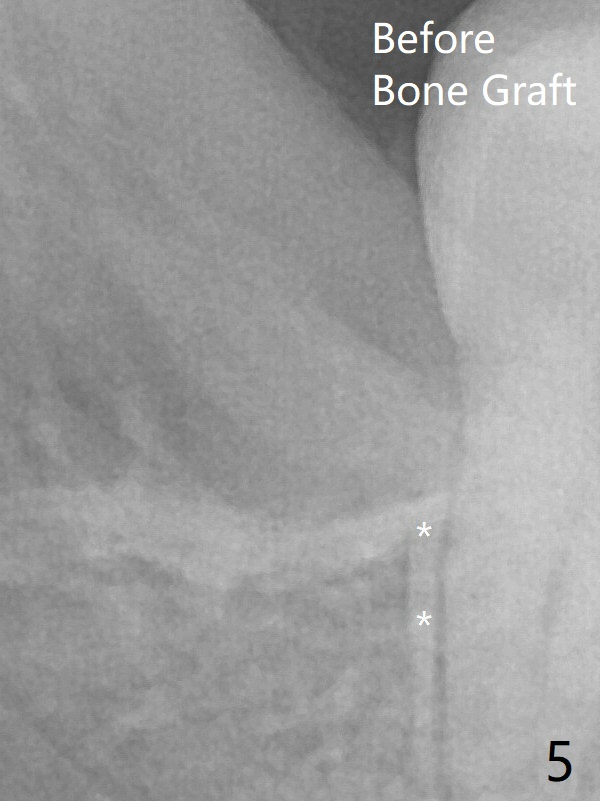

The transverse cortex connecting to the lamina dura (Fig.5 *) is obliterated when allograft is placed (Fig.7 G). The part of the graft remains in place 1 month postop (Fig.9) in spite of wound dehiscence (Fig.8). The bone graft loss is indicated by the fact of the reappearance of the transverse cortex (Fig.9).